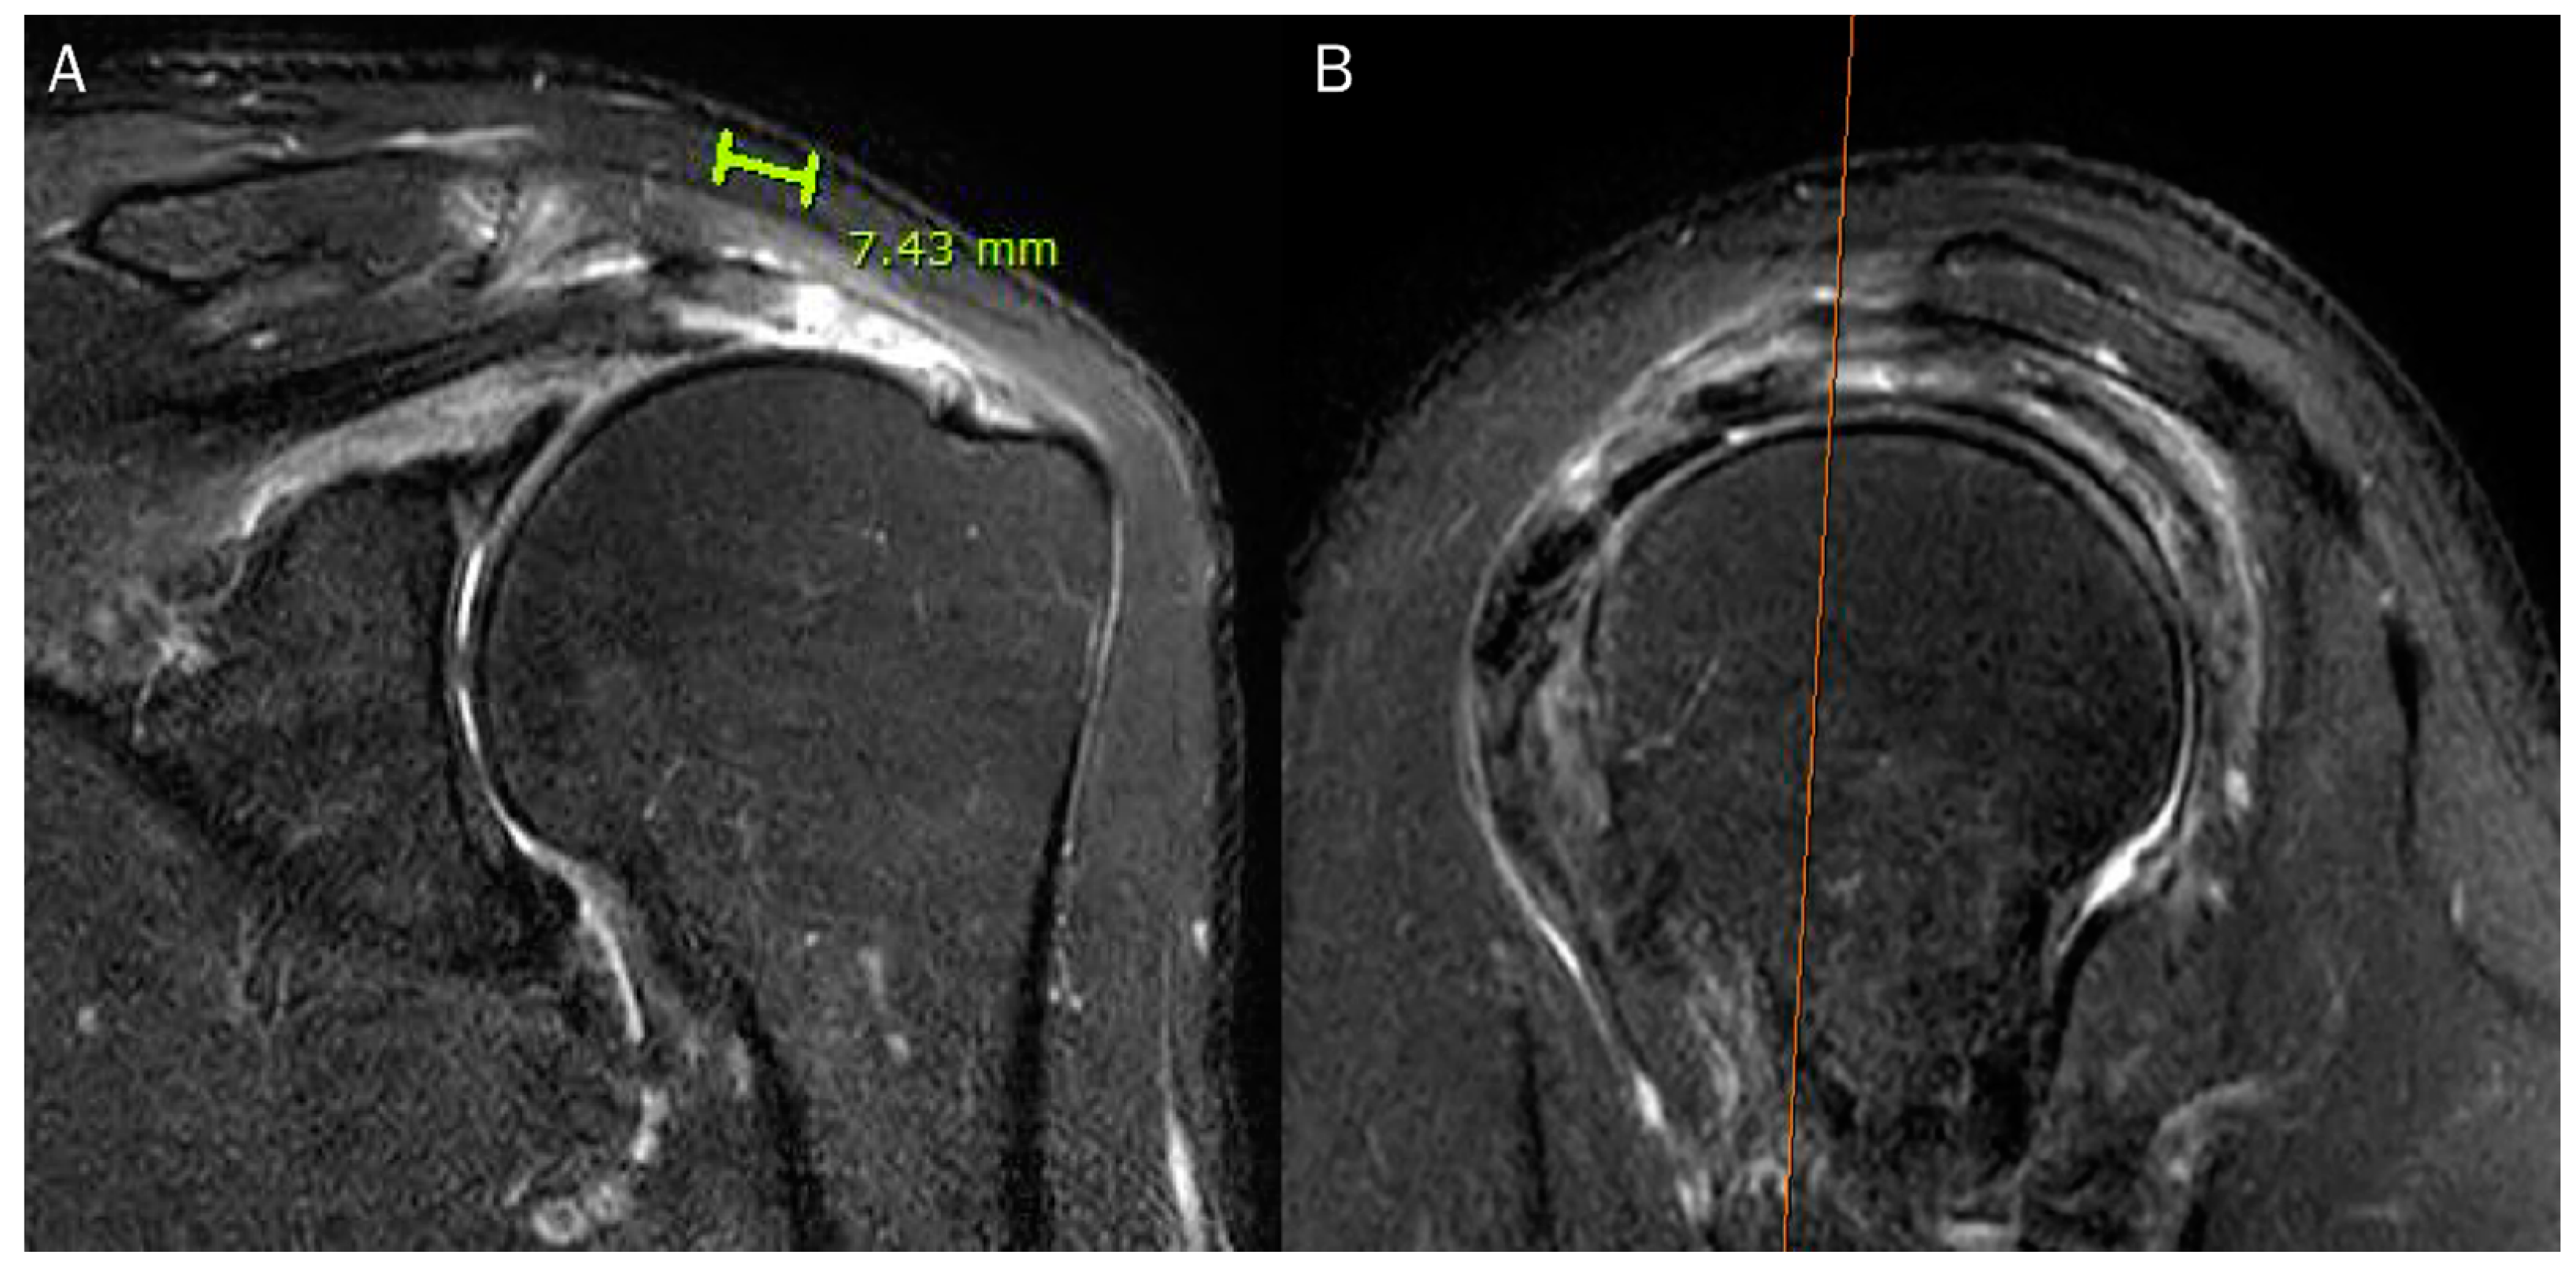

| 2 | retraction length of the articular and bursal layers |

| length of the intrasubstances cleavage | |

| length of the anteroposterior tear | |